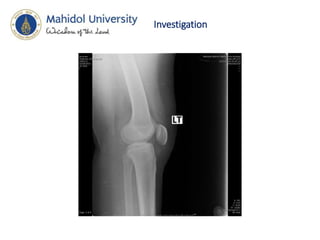

Investigation

• Film femur AP , lat

• Hip AP,lat

• Knee AP,lat

Diagnosis • Close fractureLt shaft of femur • Swelling of Lt knee